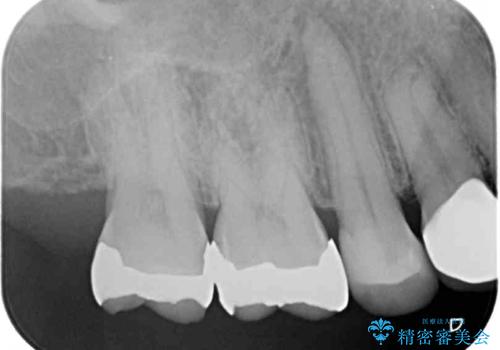

銀歯の下の虫歯はそれほど大きくなく、初回の処置以降、痛みを感じることはなくなりました。

セラミックインレー装着後も痛みが生じることはなく、神経の状態も正常な反応が認められました。